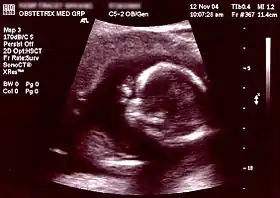

| Non-invasive | Ultrasound detection | Commonly dating scans (sometimes known as booking scans or dating ultrasounds) from 7 weeks to confirm pregnancy dates and look for multiple pregnancies. The specialised nuchal scan at 11–13 weeks may be used to identify higher risks of Downs syndrome. Later morphology scans, also called anatomy ultrasound, from 18 weeks may check for any abnormal development. Additional ultrasounds may be performed if there are any other problems with the pregnancy, or if the pregnancy is post-due. | First or second trimester |

At early presentation of pregnancy at around 6 weeks, early dating ultrasound scan may be offered to help confirm the gestational age of the embryo and check for a single or twin pregnancy, but such a scan is unable detect common abnormalities. Details of prenatal screening and testing options may be provided.

Around weeks 11–13, nuchal translucency scan (NT) may be offered which can be combined with blood tests for PAPP-A and beta-hCG, two serum markers that correlate with chromosomal abnormalities, in what is called the First Trimester Combined Test. The results of the blood test are then combined with the NT ultrasound measurements, maternal age, and gestational age of the fetus to yield a risk score for Down Syndrome, Trisomy 18, and Trisomy 13. First Trimester Combined Test has a sensitivity (i.e. detection rate for abnormalities) of 82–87% and a false-positive rate around 5%.[18]

The anomaly scan is performed between 18–22 weeks of gestational age. The International Society of Ultrasound in Obstetrics and Gynecology (ISUOG) recommends that this ultrasound is performed as a matter of routine prenatal care, to measure the fetus so that growth abnormalities can be recognized quickly later in pregnancy, and to assess for congenital malformations and multiple pregnancies (i.e. twins).[19] The scan can detect anencephaly, open spina bifida, cleft lip, diaphragmatic hernia, gastrochisis, omphalocele, congenital heart defect, bilateral renal agenesis, osteochondrodysplasia, Edwards syndrome, and Patau syndrome.[20]

Ultrasound of a fetus, which is considered a screening test, can sometimes miss subtle abnormalities. For example, studies show that a detailed 2nd trimester ultrasound, also called a level 2 ultrasound, can detect about 97% of neural tube defects such as spina bifida . Ultrasound results may also show "soft signs," such as an Echogenic intracardiac focus or a Choroid plexus cyst, which are usually normal, but can be associated with an increased risk for chromosome abnormalities.